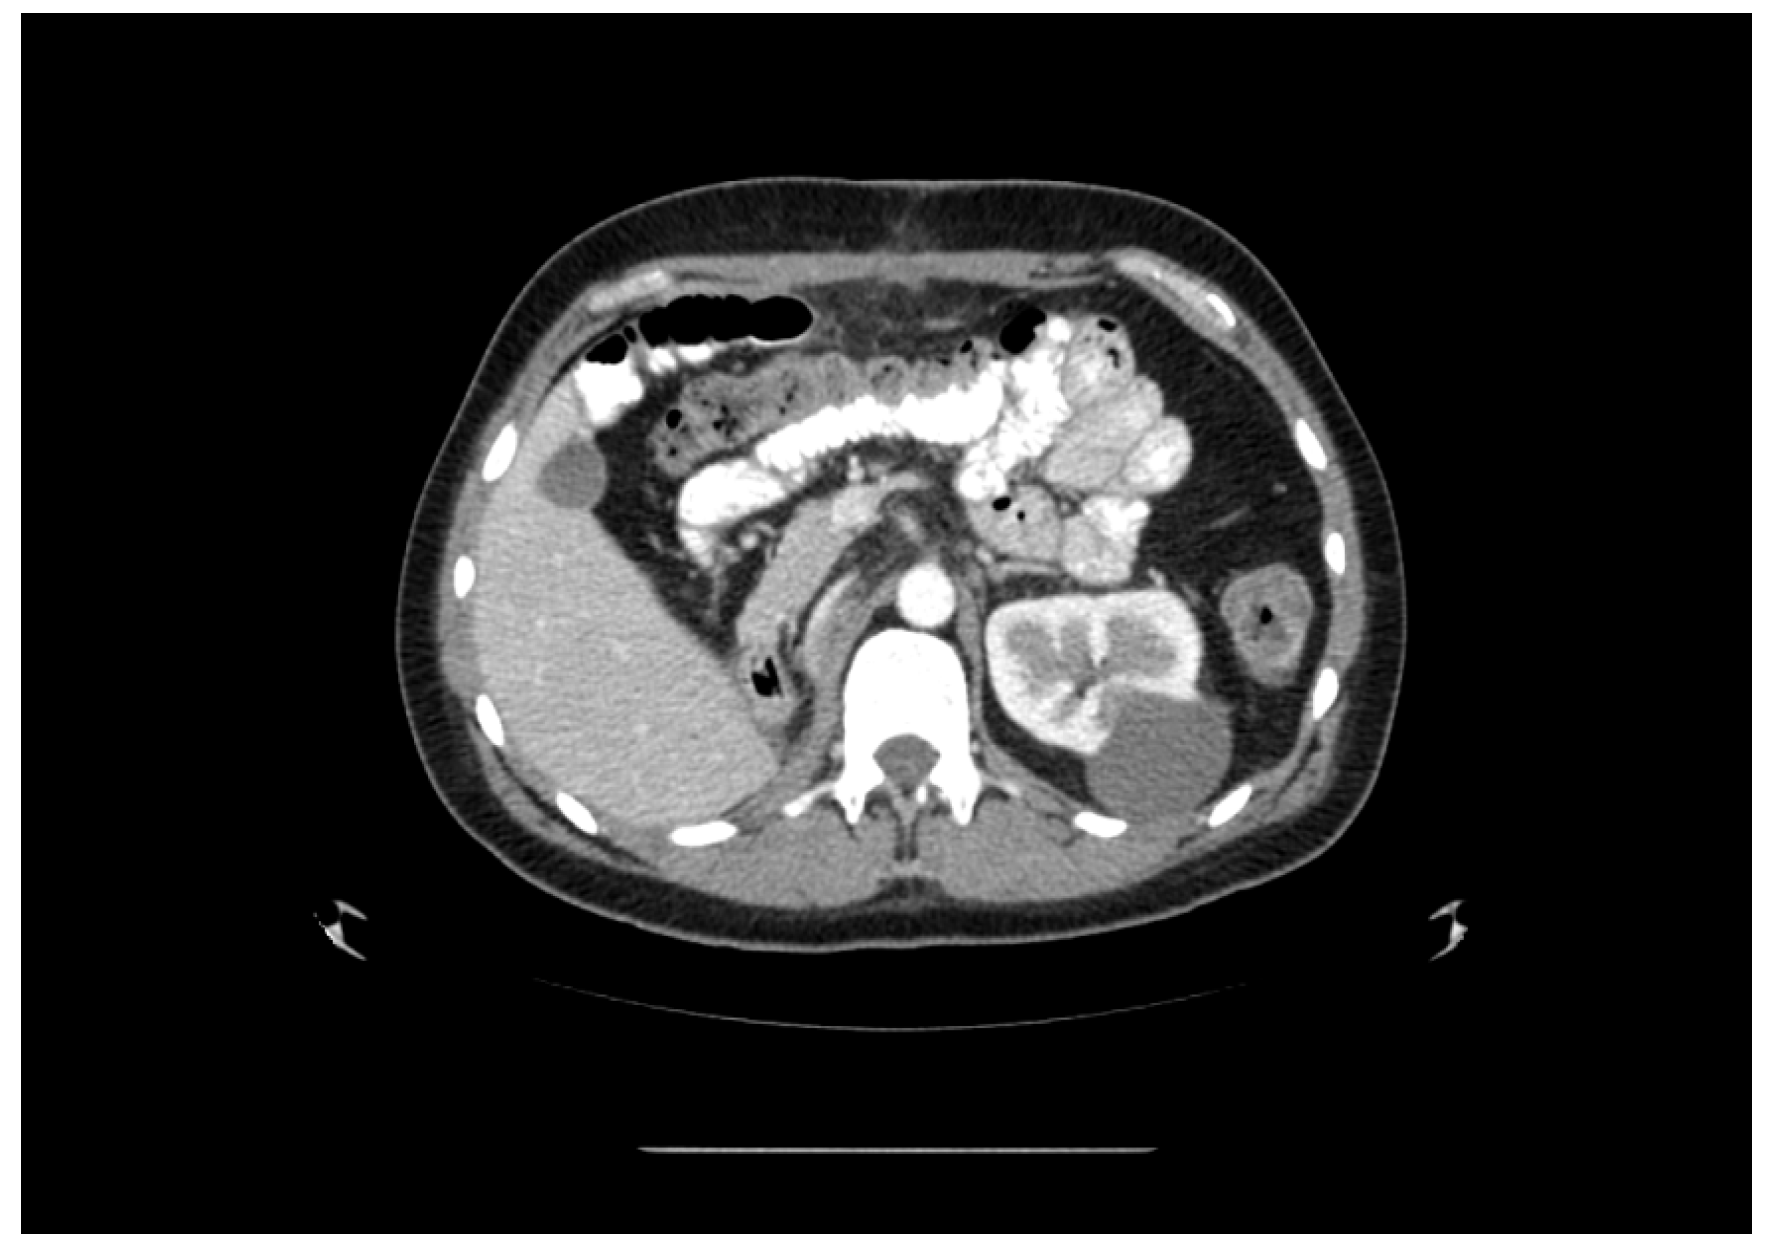

2. Case Presentation